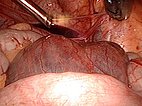

Image during laparoscopic resection: view from the umbilicus to the lower abdomen with some free fluid on the bladder. A large retroperitoneal cyst (lymphatic malformation) bulges in front.